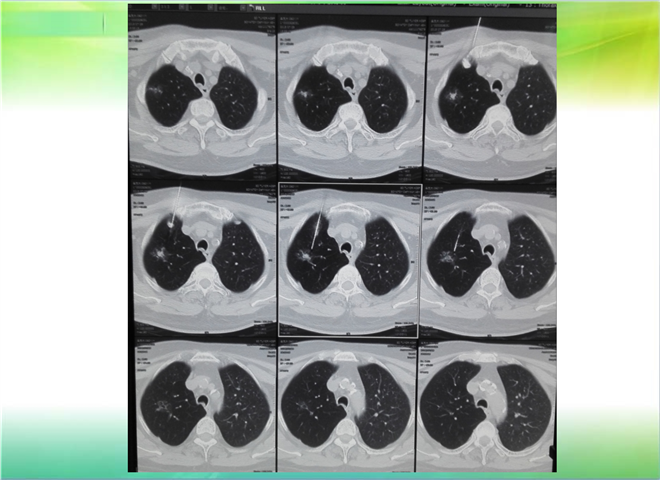

CT引导下穿刺活检术